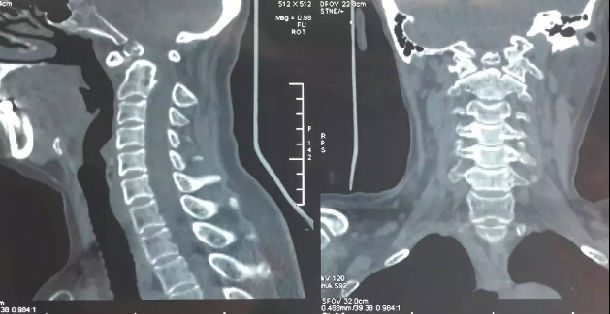

3影像学检查

手术前前屈位X光片寰枢椎脱位(寰齿前间隙7mm)。寰枢椎三维CT见寰枕融合,颅底陷入(齿状突位于钱氏线上14.2mm),右侧枢椎椎弓根发育狭小(小于2mm),磁共振显示小脑扁桃体下疝、颈髓损伤伴椎管狭窄。

4术前片子